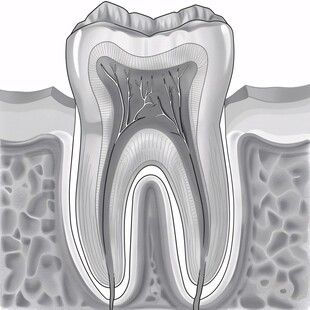

牙齿结构剖面 商用作品

牙齿结构剖面 商用作品 -

牙齿结构图 非商作品

牙齿结构图 非商作品 -

牙齿结构牙齿解剖 非商作品

牙齿结构牙齿解剖 非商作品 -

牙龈牙齿截面示意图 商用作品

牙龈牙齿截面示意图 商用作品 -

牙齿解剖图 非商作品

牙齿解剖图 非商作品 -

牙齿结构图 共享分: 80

牙齿结构图 共享分: 80 -

牙齿结构 共享分: 30

牙齿结构 共享分: 30 -

口腔结构牙齿结构 共享分: 100

口腔结构牙齿结构 共享分: 100 -

牙齿的结构 共享分: 100

牙齿的结构 共享分: 100 -

牙齿结构图 共享分: 200

牙齿结构图 共享分: 200 -

牙齿结构图 共享分: 100

牙齿结构图 共享分: 100 -

牙齿结构 共享分: 100

牙齿结构 共享分: 100 -

牙齿结构图 共享分: 40

牙齿结构图 共享分: 40 -

牙齿解刨图 共享分: 80

牙齿解刨图 共享分: 80 -

牙齿解剖图 共享分: 100

牙齿解剖图 共享分: 100 -

牙齿形态解剖图 共享分: 100

牙齿形态解剖图 共享分: 100 -